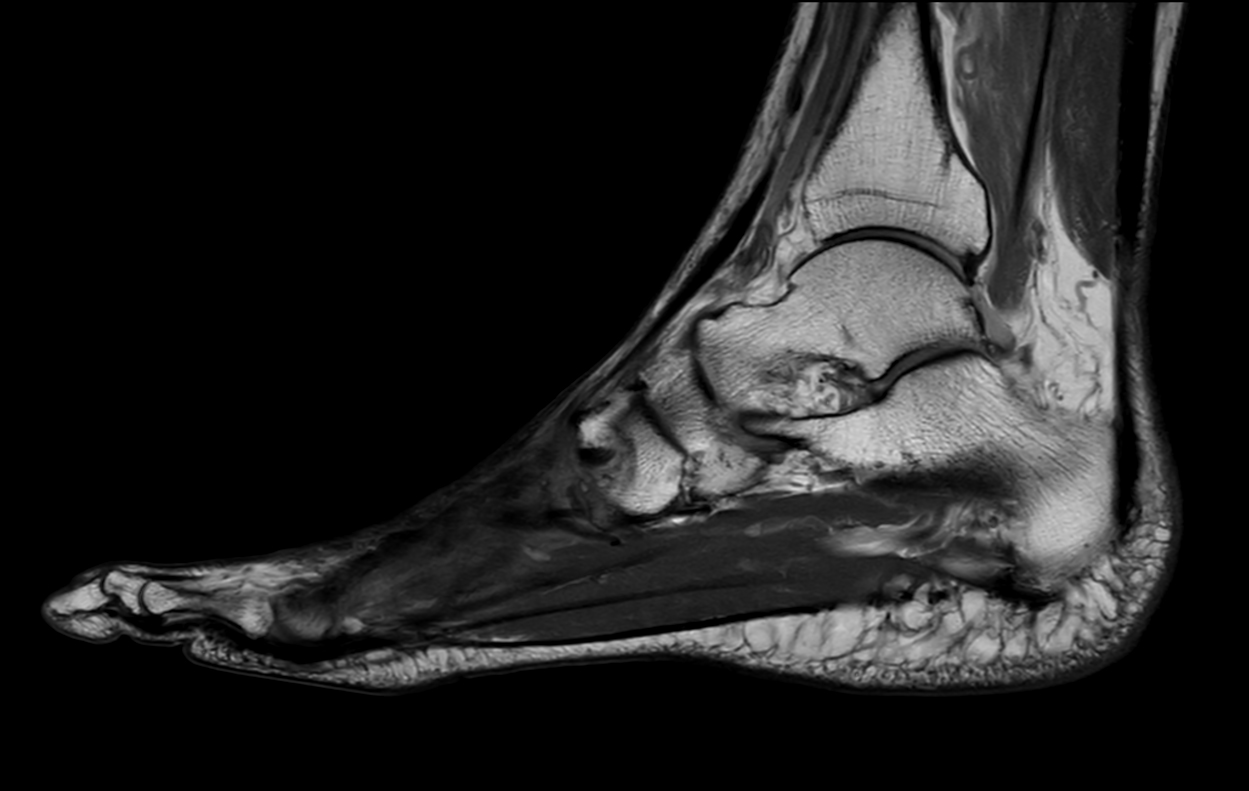

Ankle/Foot imaging post-amputation

Patient with partial amputation of the foot

Sagittal PDw mDIXON XD TSE (Water only)

-

Sagittal PDw mDIXON XD TSE (In Phase)

Sagittal PDw mDIXON XD TSE (Partial FatSat)